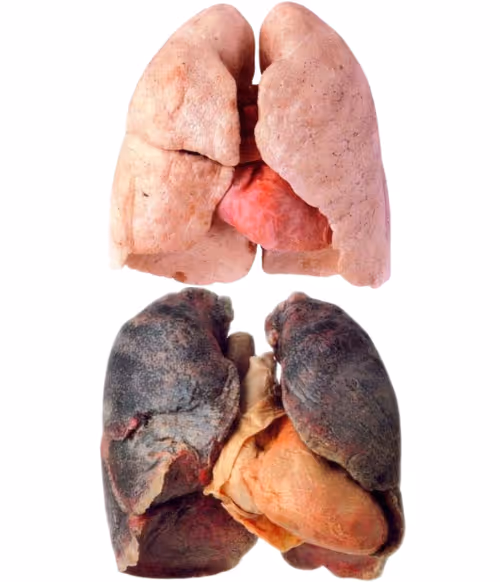

A chronic, inflammatory lung disease that causes obstructed airflow from the lungs. Emphysema (caused by the destruction of air sacs, and alveoli) and Chronic Bronchitis are the most common conditions that make up COPD.

Symptoms include breathing difficulties, cough, mucus, and wheezing. It is caused typically by long-term exposure to breathable irritants. The disease is progressive and currently irreversible. Patients are at increased risk of developing heart disease, lung cancer, and a variety of other conditions.

The model organism used is an elastase enzyme-treated rat. The enzyme damages a significant number of lung air sacs (alveoli) mimicking the case of lung emphysema in patients.

Testing the effect of SMS cells instilled into the lung of this rat resulted in a high percentage of alveoli regeneration using a mere single dose of SMS cells. Different regimens are currently being studied to optimize the healing effect of these cells.